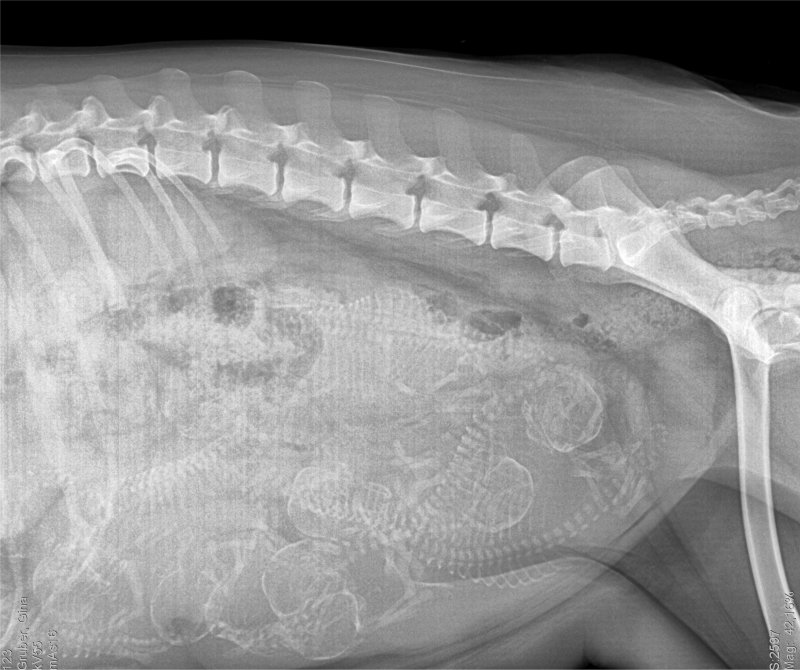

Voraussichtlicher Geburtstermin 19.09.2018

Wir sind schon gewachsen: (Röntgenbild)